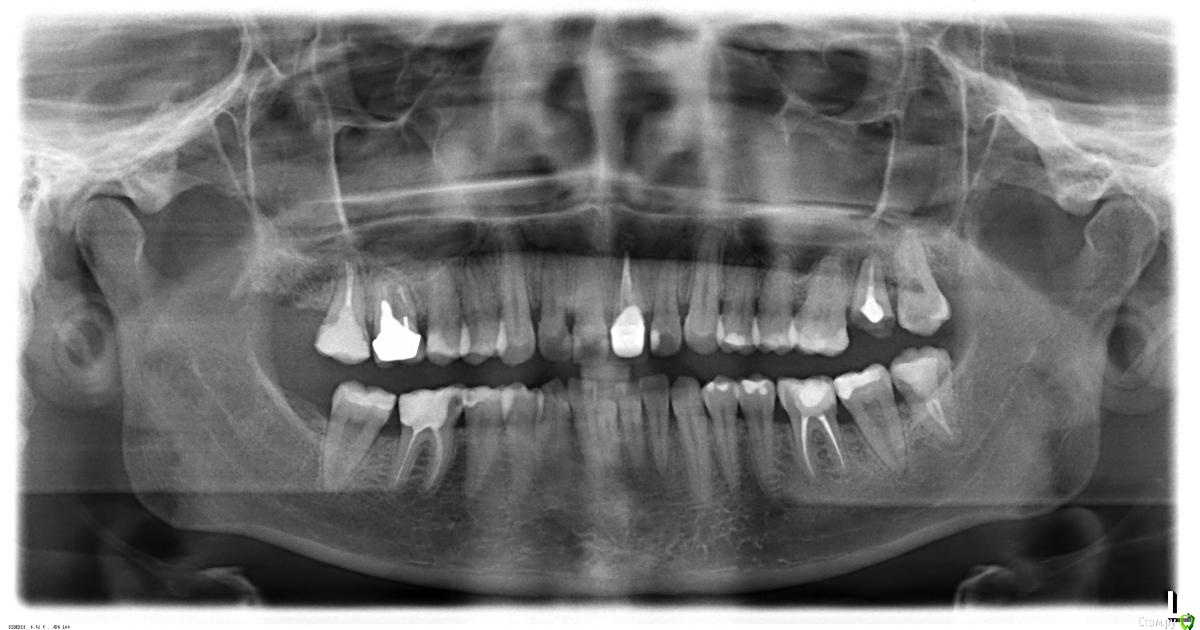

l_yulia Опубликовано 21 июля, 2015 Поделиться Опубликовано 21 июля, 2015 С этим зубом долгая история. 7 лет назад у меня там была киста и одновременно беременность, а когда беременность закончилась, а киста была вылечена, то в оставшийся корень вставили стекловолоконный штифт и на него коронку. Коронка металлокерамическая, врач мне сказала тогда, что поставить безметалловую керамику нельзя (видимо им просто почему-то так было удобнее). Коронка была толще чем мой собственный зуб и именно это стало причиной того что в конце-концов коронка вместе со штифтом вывалилась (я ее как бы все время толкала нижними зубами).Так как финансовой возможности в момент выпадения коронки никакой не было от слова совсем, то я решила приклеивать его каждый день на корегу, и регуляно полоскать антисептиками. Но на прошлой неделе, когда я ела персик, коронка внезапно отклеилась, а я не сразу заметала и продолжила кусать персик, потом услышала хруст и поняла, что придется уже решать как-то проблему. Скорее всего я все таки сломала корень, так как потом 2 дня были не очень приятные ощущения в области зуба.В прошлую пятницу и субботу я записалась в 3 стоматологических клиники на консультацию на счет имплантации. Я хотела одномоментную с удалением корня имплантацию, и желательно чтоб можно было сразу установить временную коронку, так как зуб передний.И вот что мне сказали в разных местах:1) Сказали, что да, можно поставить сразу. В той клинике используют только 2 системы имплантов ("Implantium" и "SuperLine"). И они мне посчитали "SuperLine". Правда сказали, что о том возможно ли будет нагружать имплант сразу станет понятно только после удаления, глядя на состояние кости, плотная она или рыхлая. И еще сказали, что обязательно потребуется пересадка кусочка кожи с неба на десну. 2) Здесь ставят разные системы ( "Miss", "Alpha bio", "AstraTech", "Implantium" и "SuperLine"). Я сказала, что думала про alpha bio и мне посчитали его, но потом врач мне аргументированно объяснил, что чтоб имплант можно было сразу нагружать он должен быть длинее собственного корня зуба, а этому требованию соответствует только "SuperLine" и что потребуется подсыпка костной ткани. И он не возражал против временной коронки и был категорически против протеза бабочки, мол он все сосочки примнет.3) Здесь ставят разные системы ( AlphaBio и MIS, Xive и Impro, Straumann, Nobel Biocare и Biohorizons, Astra Tech) Врач сказал мне, что нет никакой разницы какой длины сам имплант и посчитал мне MIS. Напугал меня тем, что при удалении оставшегося корня зуба у меня не останется передней стенки (если поставить имплант одномоментно, то он будет просвечивать) и лучше будет, если сначала удалить зуб, а имплант поставить через 2 недели, когда кровяной сгусток видоизменится в костную ткань. Он был категорически против сразу ставить временную коронку и был за протез бабочку, когда я спросила про сосочки, то он сказал, что мы так сделаем протез, что ничего не примнем.А теперь мне хочется здесь на форуме получить независимую консультацию и понять, какой имплант лучше, действительно ли он должен быть длинее собственного корня или это не имеет никакого значения?Правда ли что у меня после удаления не останется переднней стенки кости?Кто из врачей, которые меня консультировали , более компетентный? КТ у меня есть. Прикрепляю 2 снимка, может на втором что-то лучше видно. один 17.07.2015, а второй примерно полугодовой давности. И фото.17.07.2015 конец 2014фото Ссылка на комментарий